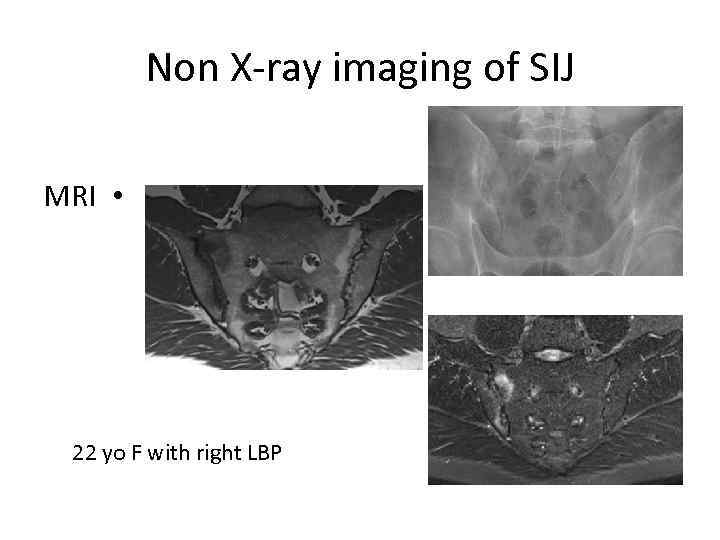

Non X-ray imaging of SIJ MRI • 22 yo F with right LBP